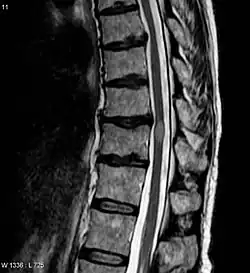

- МРТ всего позвоночника с контрастным усилением и без него (Данное исследование позволит оценить насколько большой очаг поражения, выявить признаки воспаления. А также исключить сдавление спинного мозга, при котором возможно оперативное лечение)

- МРТ головного мозга с контрастным усилением гадолинием и без него. (Для оценки наличия очагов демиелинизации в головном мозге, что может указывать на рассеянный склероз)

- Частичный поперечный миелит: по данным магнитно-резонансной томографии вовлечены один-два сегмента спинного мозга. При осмотре симптомы могут быть ассиметричными.

- Полный поперечный миелит: поражение симметричное и тяжелое, относится к дисфункции спинного мозга, которая вызывает симметричный, полный или почти полный неврологический дефицит ниже уровня поражения (значительное нарушение двигательной функции, потеря чувствительности и вегетативная дисфункция). При нейровизуализации: поражение, распространяющееся на один-два сегмента.

- Продольно-распространенный поперечный миелит: поражение спинного мозга может быть полным или неполным, а распространённость по данным магниторезонансной томографии составляет три или более сегмента спинного мозга.